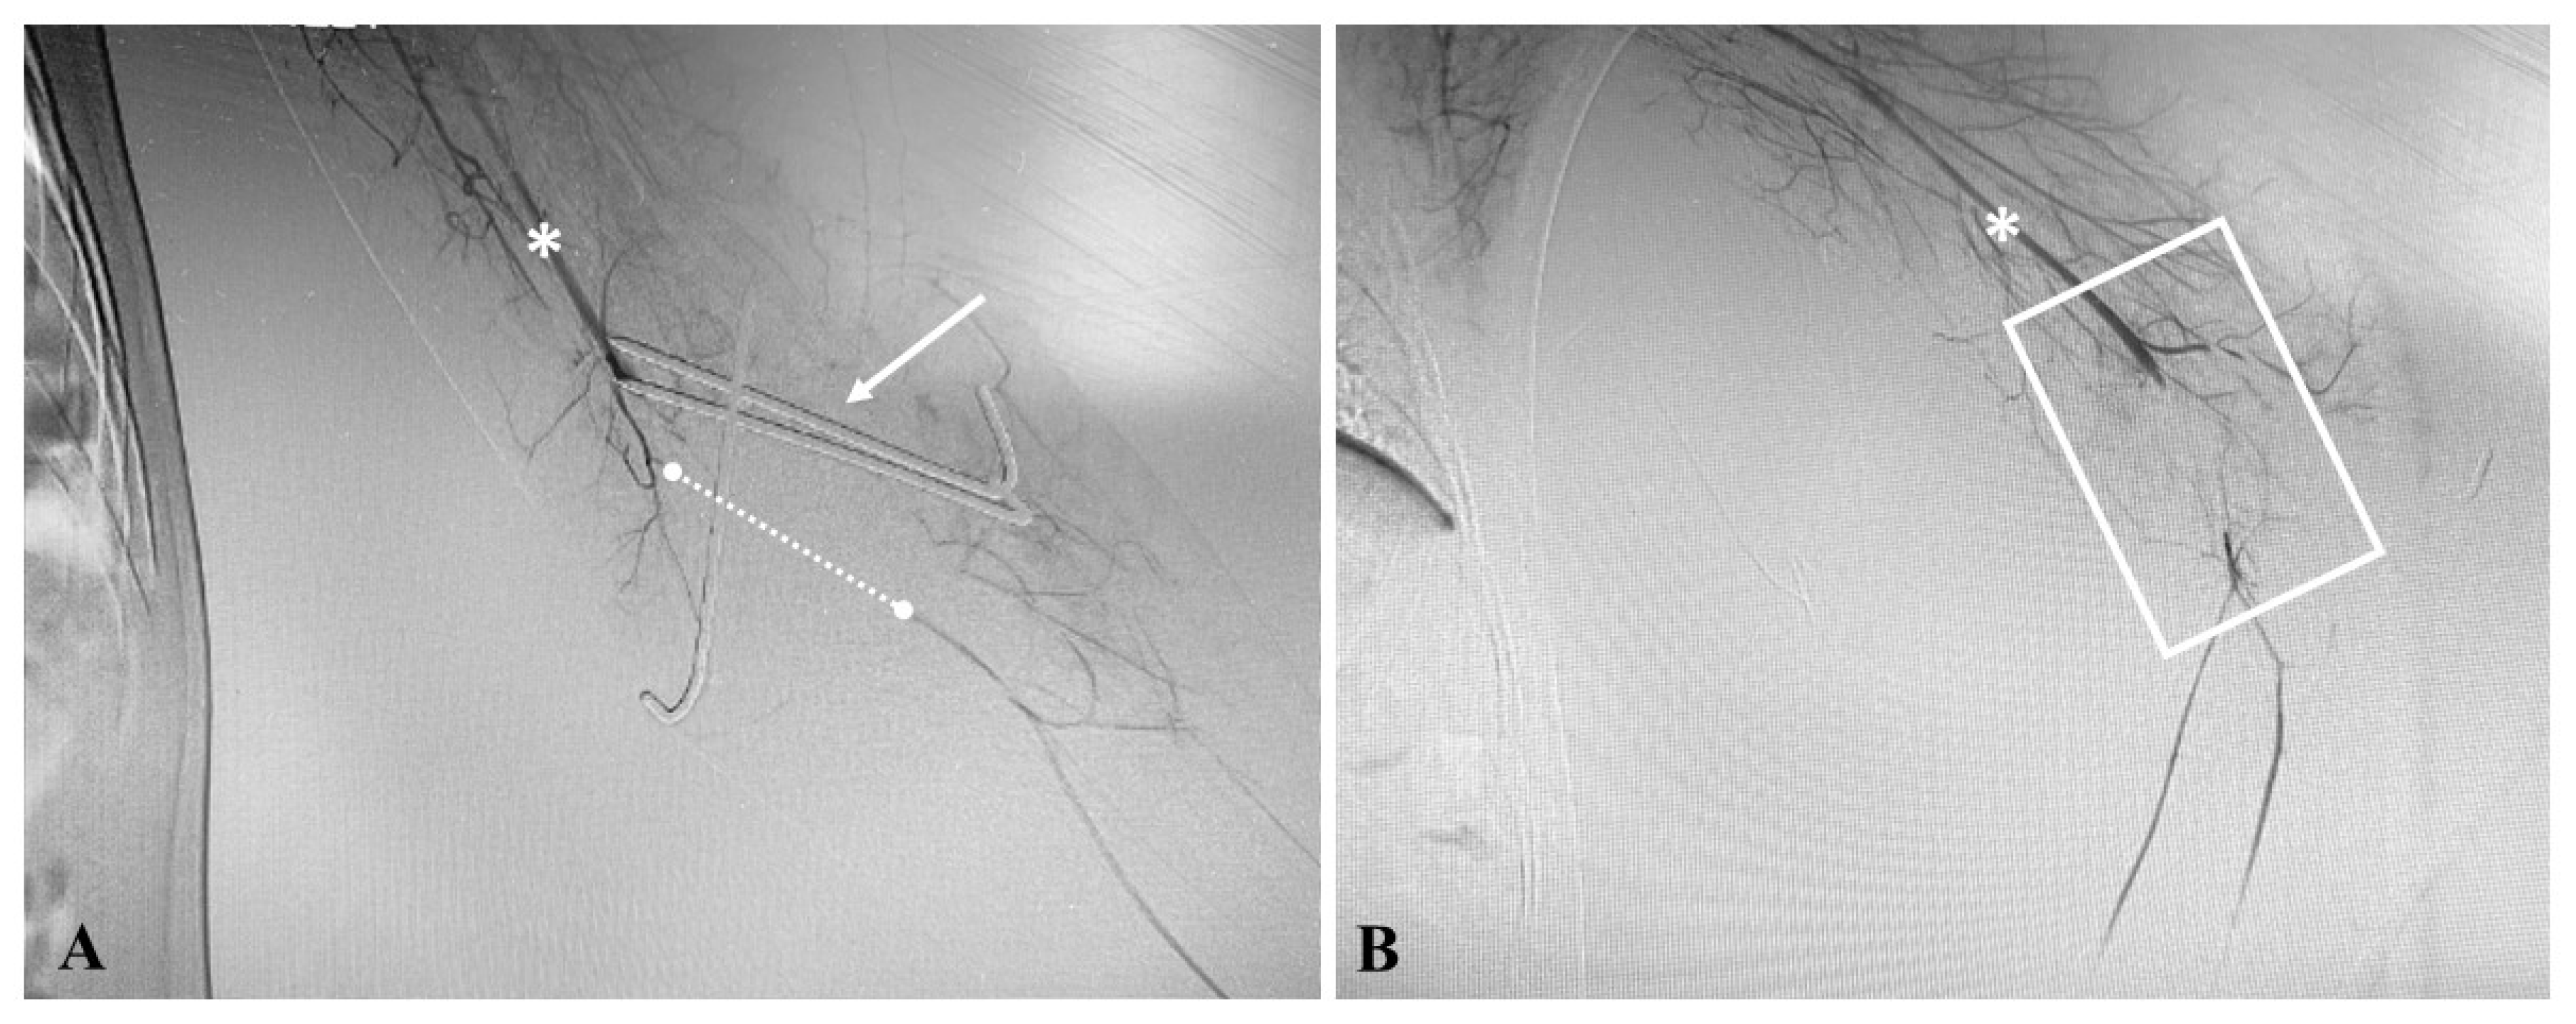

3.1. Institutional Case Report #1—Upper Extremity Injury and Open Surgery